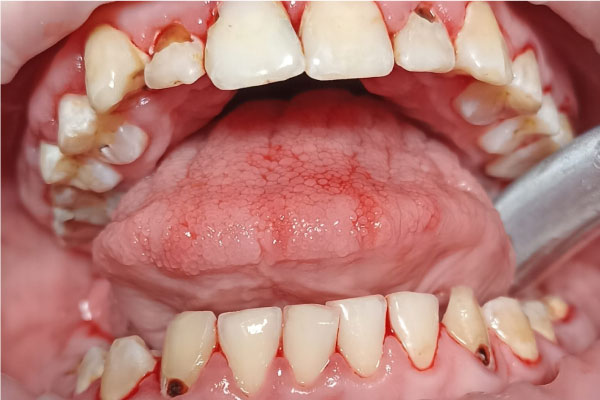

Наши работы

Фото ДО

Фото ПОСЛЕ

Наведите для просмотра

Профессиональная гигиена молочных зубов